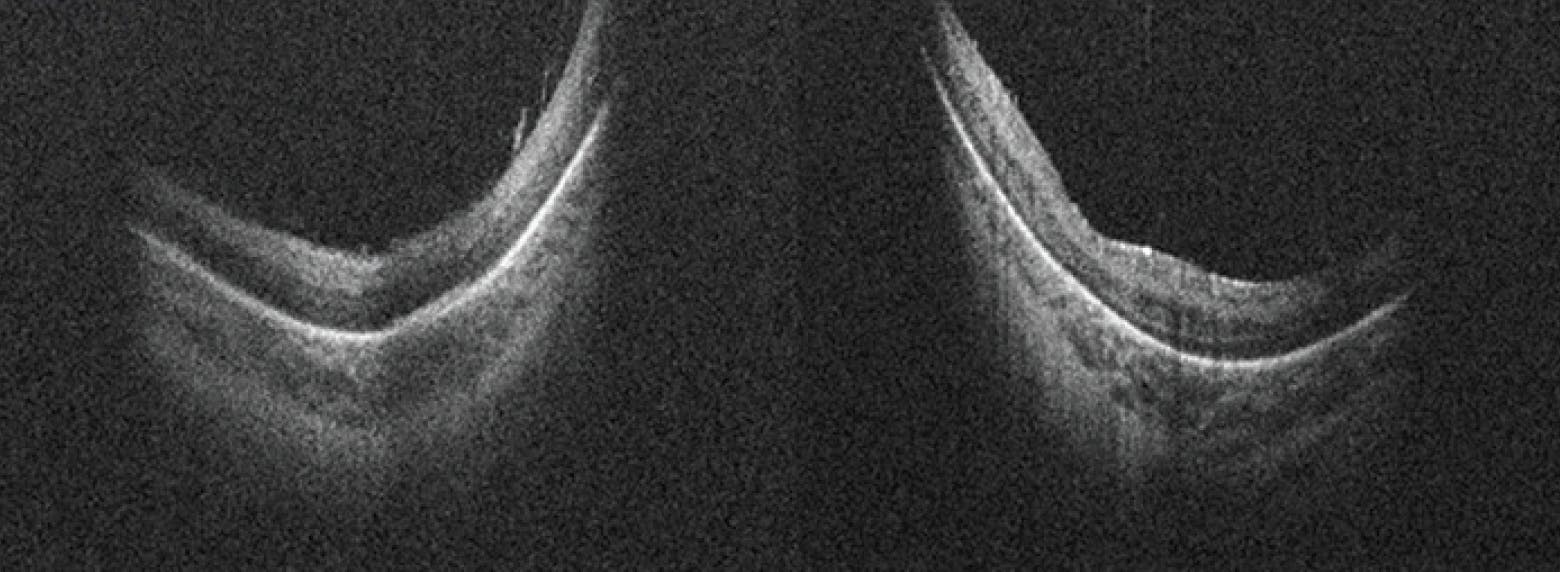

A 2-year-old girl presented with dimness of vision with nystagmus in each eye for 9 months. Dilated fundus examination of each eye revealed peripheral pigmentary changes sparing the posterior pole (Figure 1), suggestive of salt and pepper retinopathy. OCT of each eye showed a maintained foveal contour. The patient was advised to undergo screening for toxoplasmosis, rubella cytomegalovirus, herpes simplex, and human immunodeficiency virus and vitamin A supplementation after consulting with her pediatrician.

<p>Figure 1. Widefield color imaging of each eye shows peripheral pigmentary changes sparing the posterior pole.</p>

Figure 1. Widefield color imaging of each eye shows peripheral pigmentary changes sparing the posterior pole.